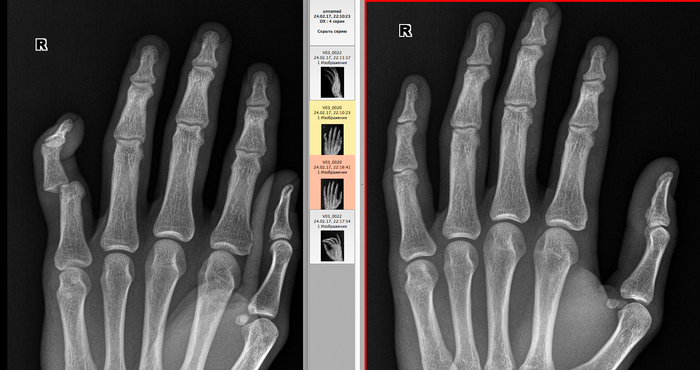

История 5

Еще одна кисть. Вывих средней фаланги 5-го пальца. На контрольной рентгенограмме справа вывих отсутствует.